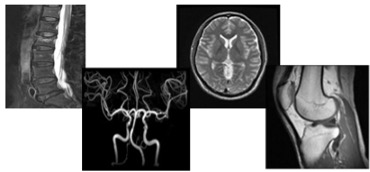

MRI検査(磁気共鳴診断撮影:Magnetic Resonance Image)

MRIとはMagnetic(磁気) Resonance(共鳴) Imaging(画像)の略で、MRIでは磁気と電波を使用して人体の横断像だけでなく、縦断像や斜めに切った像などあらゆる方向の断層面の撮影が容易にできます。

当院では1.5T(テスラ:磁石の強さを表す単位)MRIと3.0テスラMRIを使用しています。